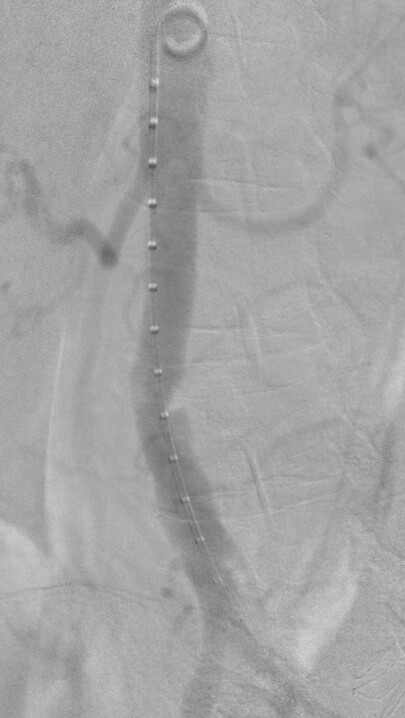

Nice image! You show the vessel in the simulated fluoro image as a surface rendering now. You can try to use the “Virtual contrast filling” section to make the appearance more realistic (the module fills the CT image uniformly inside the segment/model with the density you specify).

Yep, that purpose was what I did not understand yet.

Virtual contrast filling can be useful to simulate stronger contrast filling (e.g., you have a CT with IV contrast injection and you want to simulate local contrast injection) or you want to add anything to the CT that was originally not there (e.g., a stent or device).

Here is the procedural image with the C-arm oriented as simulated. I find it a faithful reproduction for a first try, and remain confident for subsequent ones.

Here it means less radio emission and less contrast medium injection.

This module should be viewed as a wonderful add-on to anyone working with a C-arm, beyond the cardio-vascular realm, orthopedists for example.